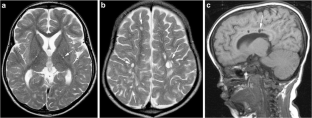

Fig. 4